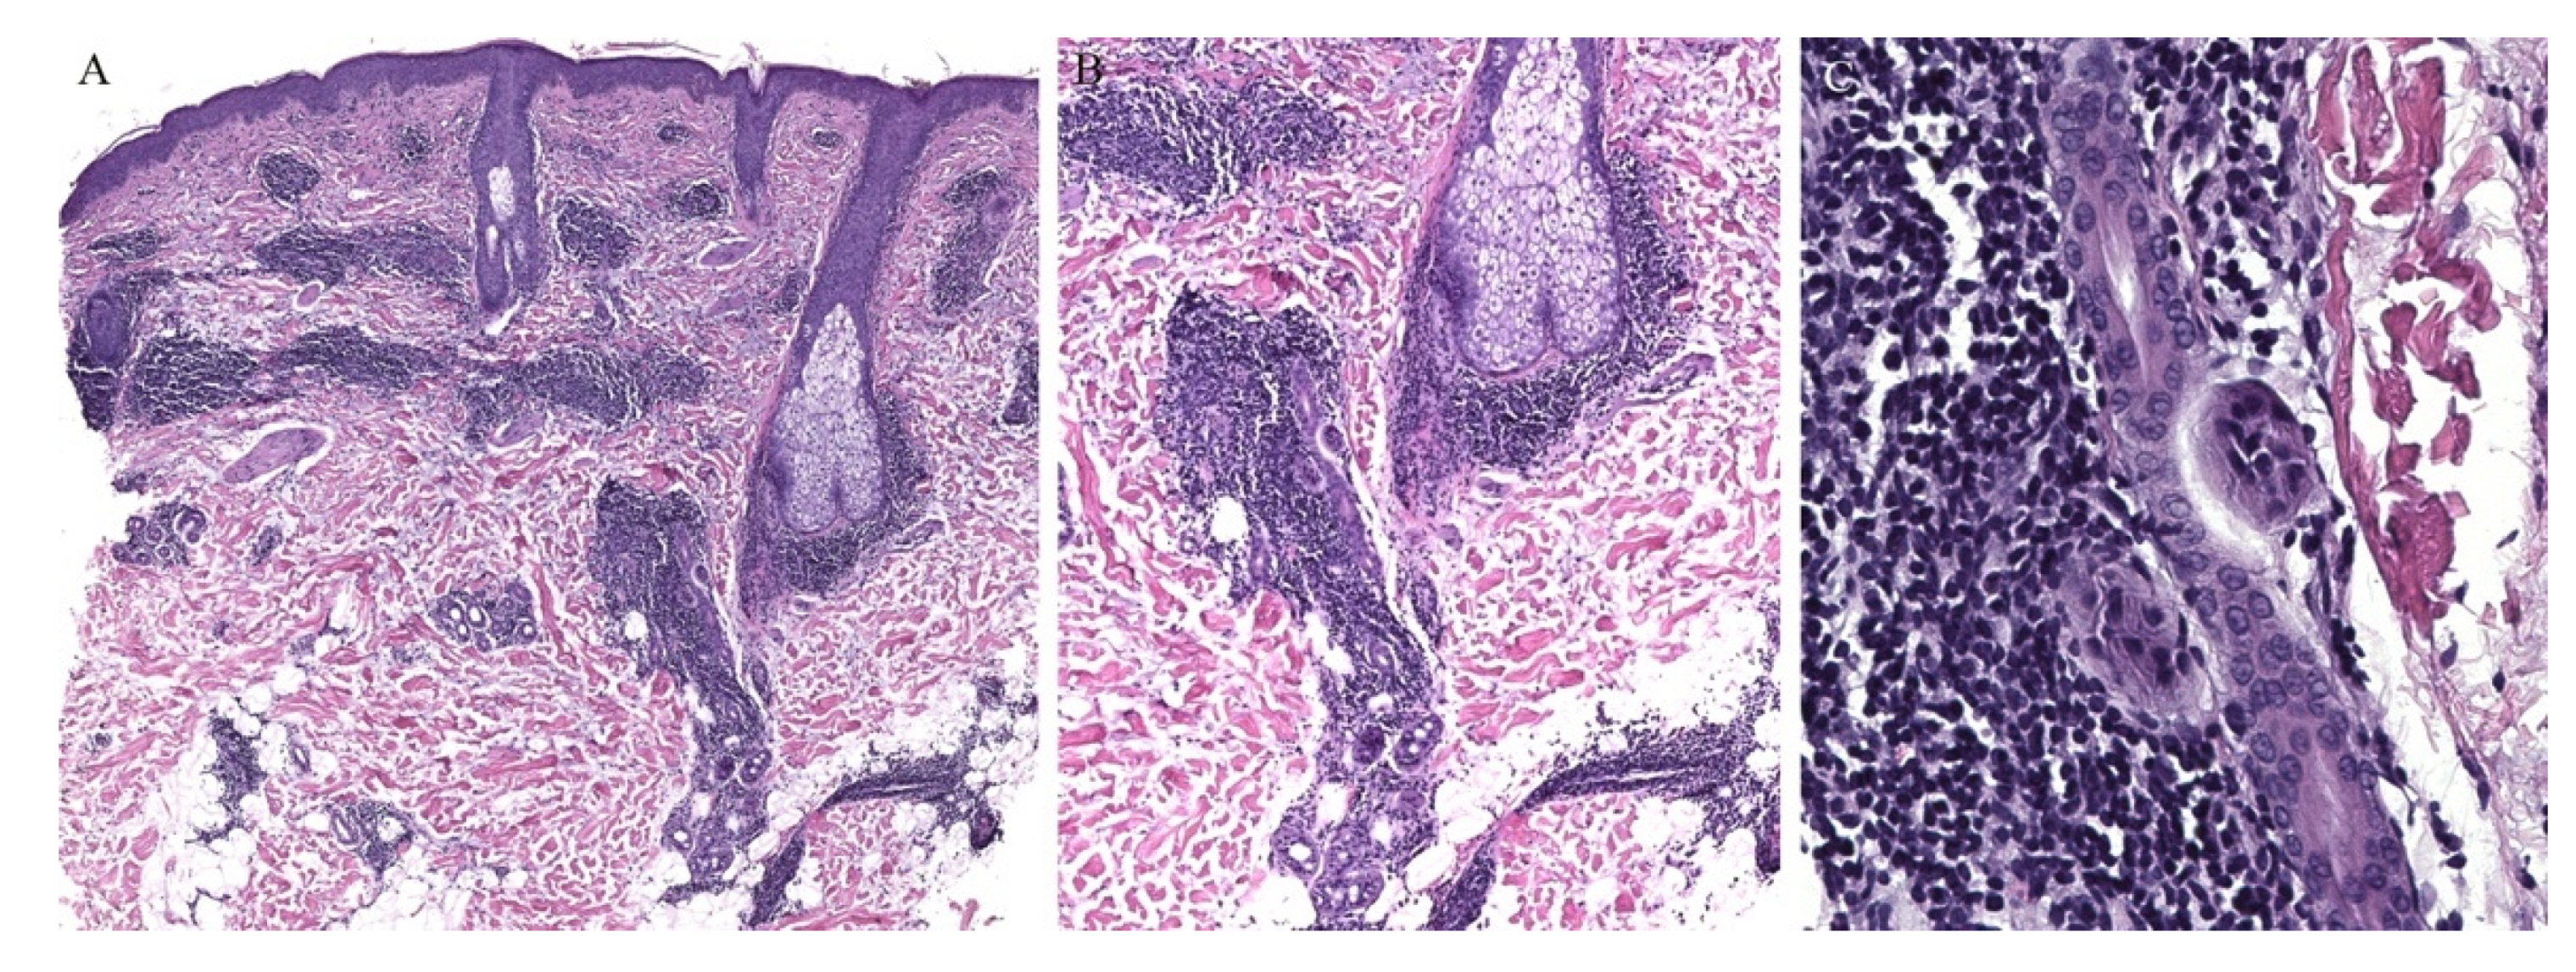

Appendageal involvement has been described. A perifollicular lymphohistiocytic inflammation has been observed in some cases of LN (Figure 3) [18,19]. In addition, a specific clinical variant of LN has been described whereby the papules had a spinous follicular appearance. On histopathology, in addition to the classical LN findings, a granulomatous infiltrate around hair follicles was noted [20,21,22]. The presence of these perifollicular granulomas led authors to emphasize that this clinical variant may be misread as lichen scrofulosorum [20].

Figure 3.

(A–C) Lichen nitidus with follicular involvement (the inset in Figure A shows a deeper section of the same case with more characteristic lichen nitidus changes).

Perieccrine inflammation has also been reported in cases of LN. A lymphocytic eccrine hidradenitis was observed in histopathological specimens of LN, not unlike perieccrine findings seen in lichen striatus [19].